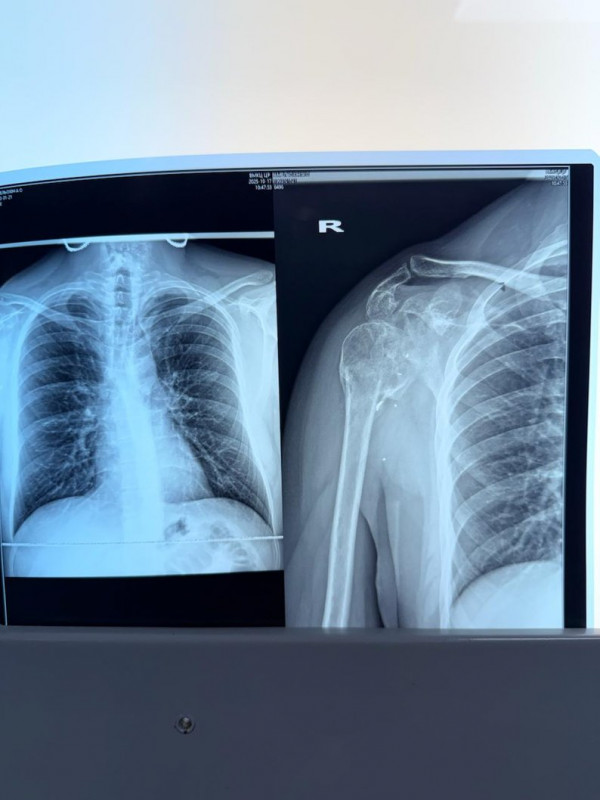

Рентгенівські знімки поранення Артура Амельохіна. Фото надав Артур Амельохін

Повномасштабне вторгнення Артур зустрів на Житомирщині, далі боронив Батьківщину на найгарячіших ділянках фронту. У квітні минулого року неподалік Покровська на Донеччині російський FPV-дрон атакував автомобіль, в якому перебував підполковник. Виконуючи обов'язки начальника штабу, Артур Амельохін повертався на командний пункт. Осколок від БпЛА пройшов через дах, розтрощивши лопатку та плечовий суглоб.

Травму медики визнали надскладною. Порятунок руки потребував нестандартного підходу, пояснив Суспільному лікар-травматолог Юрій Лазаренко. Унікальність випадку Артура — у комплексному руйнуванні: дрон знищив не лише суглоб, а й лопатку — каркас, до якого кріпляться м'язи.

"Тут поранення FPV-дроном і комплексне руйнування плечового суглобу. Руйнування лопатки. Ми робили тут в декілька етапів оперативне втручання. Першим етапом ми відновили саму структуру лопатки, за рахунок остеосинтезухірургічний метод лікування переломів, який передбачає точне зіставлення (репозицію) уламків кістки та їх стабільну фіксацію спеціальними металевими конструкціями (пластинами, гвинтами, штифтами) до повного зрощення, і тоді ж ми встановили індивідуальний цементний спейсертимчасовий імплантат, що виготовляється з кісткового цементу з антибіотиком для заміщення дефектів кісток та лікування перипротезної інфекції (особливо кульшового/колінного суглобів)", — розповів лікар.